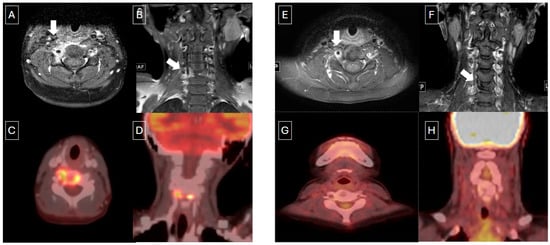

3.1.2. Re-Staging or Assessment of Disease Reactivation by PET Scans

3.1.3. Assessment of Response to Therapy by PET Scans